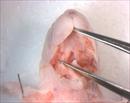

| Mutant 012-003-2 (E16.5) has polydactly | Cplane1b2b012Clo/Cplane1b2b012Clo | C57BL/6J-Cplane1b2b012Clo |

| Mutant 012-003-2 (E16.5) has a cleft palate | Cplane1b2b012Clo/Cplane1b2b012Clo | C57BL/6J-Cplane1b2b012Clo |